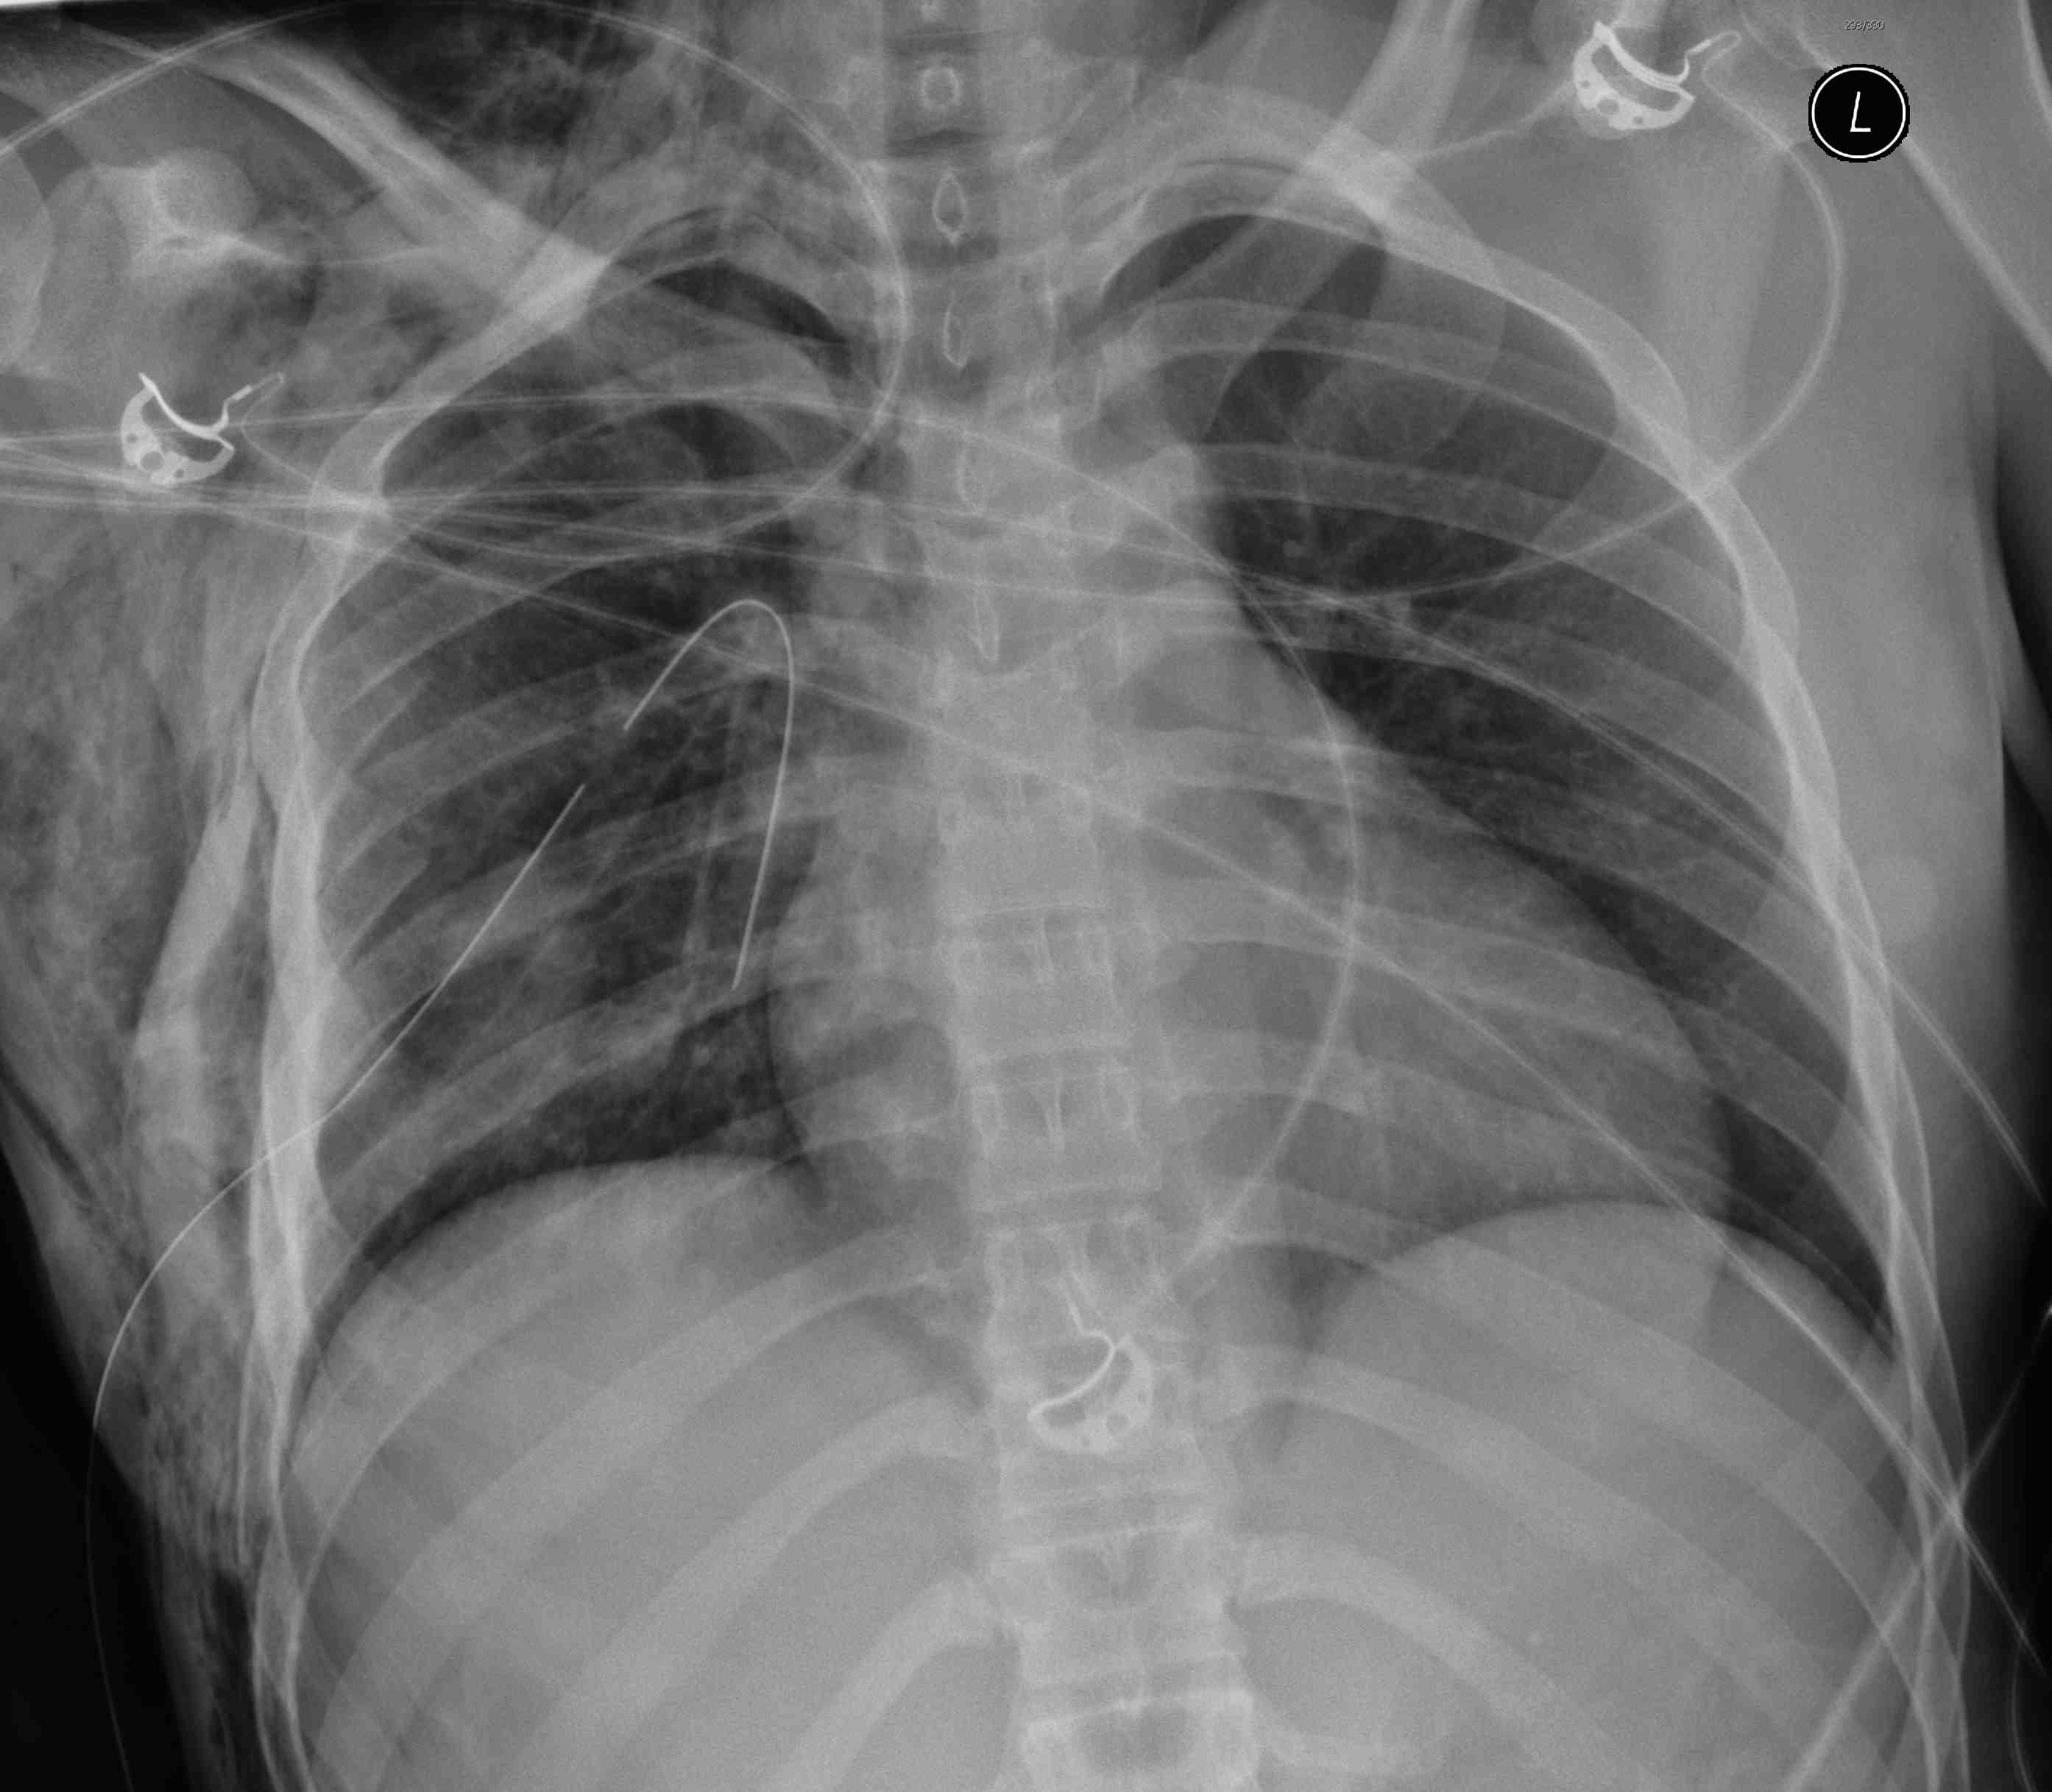

Pneumothorax / haemothorax

- decreased breath sounds

Tension pneumothorax

- heart apex and trachea displaced

- heart sounds (muffled + distended neck veins = cardiac tamponade)

Hemothorax / Indications for thoracotomy

- > 1500 mls blood

- > 250 mls per hour for 4 hours

- CXR (hemothorax / widened mediastinum)

Trauma Series

- lateral C spine / CXR / AP pelvis